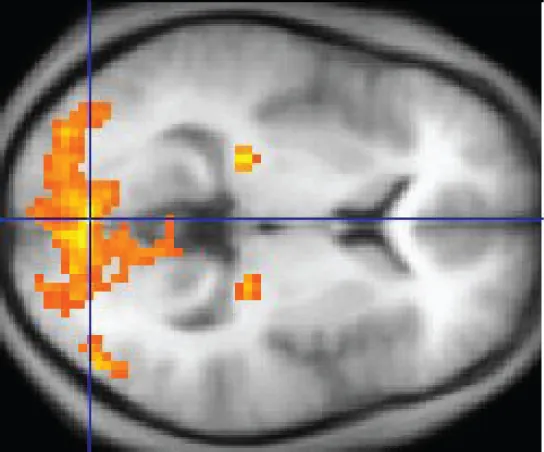

An easy way to see how much of the brain a person uses is to take measurements of brain activity while performing a task. An example of this kind of measurement is functional magnetic resonance imaging (fMRI), which generates a map of the most active areas and can be generated and presented in three dimensions (Figure 12.7). This procedure is different from the standard MRI technique because it is measuring changes in the tissue in time with an experimental condition or event.

This MRI image shows a grainy computer readout of a cross section of the brain. The anterior side of the brain, located on the right hand side of the image, has a large area lighting up with yellow, indicating neural stimulation. Two smaller regions at the center of the brain are also yellow. The two small areas are in the same relative location but in opposite hemispheres of the brain.

Figure 12.7 fMRI This fMRI shows activation of the visual cortex in response to visual stimuli. (credit: “Superborsuk”/Wikimedia Commons)

The underlying assumption is that active nervous tissue will have greater blood flow. By having the subject perform a visual task, activity all over the brain can be measured. Consider this possible experiment: the subject is told to look at a screen with a black dot in the middle (a fixation point). A photograph of a face is projected on the screen away from the center. The subject has to look at the photograph and decipher what it is. The subject has been instructed to push a button if the photograph is of someone they recognize. The photograph might be of a celebrity, so the subject would press the button, or it might be of a random person unknown to the subject, so the subject would not press the button.

In this task, visual sensory areas would be active, integrating areas would be active, motor areas responsible for moving the eyes would be active, and motor areas for pressing the button with a finger would be active. Those areas are distributed all around the brain and the fMRI images would show activity in more than just 10 percent of the brain (some evidence suggests that about 80 percent of the brain is using energy—based on blood flow to the tissue—during well-defined tasks similar to the one suggested above). This task does not even include all of the functions the brain performs. There is no language response, the body is mostly lying still in the MRI machine, and it does not consider the autonomic functions that would be ongoing in the background.